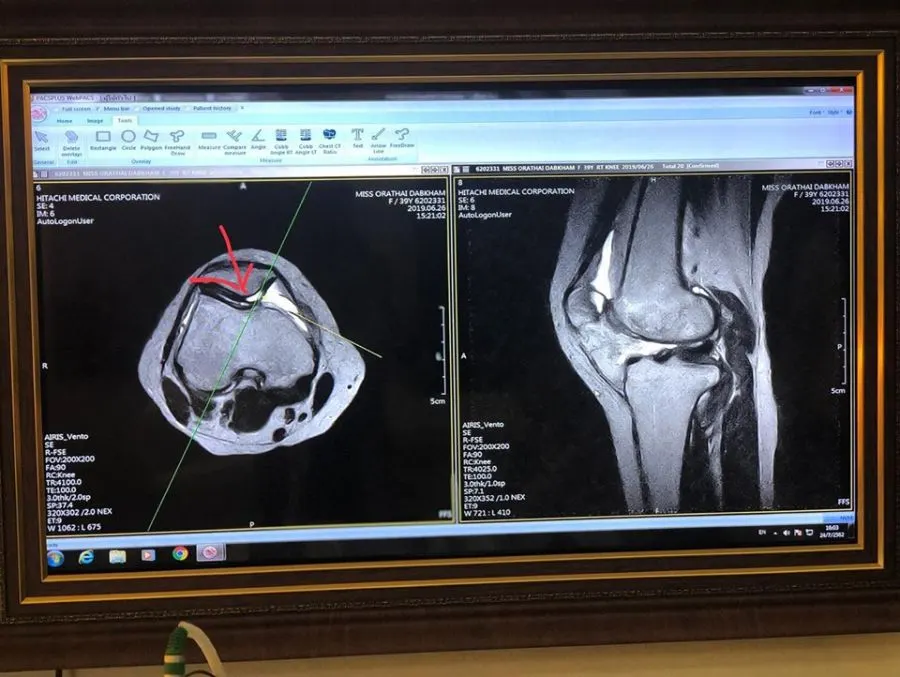

‘ต่าย อรทัย’รู้ความจริงทรมานเข่าพัง ลุ้นหายกลับมาวิ่งได้ วันนี้ (25 ก.ค.) นักร้องลูกทุ่งสาวคันดัง “ต่าย อรทัย” ได้โพสต์ข้อความในเฟซบุ๊ก Tai Orathai ว่า ปวดข้อ ปวดหลัง ทั้งพี่ทั้งน้อง .. MRI ให้รู้ว่ากระดูก เส้นเอ็น เส้นประสาท เป็นอะไร ตรงไหน จะได้รักษาได้ตรงจุด .. ขออัพเดทอาการบาดเจ็บข้อเข่าให้ทุกคนทราบนะคะ .. ผ่านคอนเสิร์ตใหญ่มา 1 เดือนเต็มๆ คอนเสิร์ตช่วงฤดูฝน มีน้อยลง ทำให้มีเวลาได้พักเยอะขึ้นตั้งแต่ 27 มิ.ย.62 ที่ผ่านมา ต่ายไป MRI (เข้าอุโมงค์ตรวจเห็นลึกถึงเส้นเอ็น เส้นประสาท และ กระดูก) ผลที่คุณหมออ่าน MRI คือ “กระดูกอ่อนหุ้มลูกสะบ้าฉีก”

คาดว่าคงฉีกมาตั้งแต่เล่นกีฬาเมื่อปลายปีที่แล้ว แต่ตอนนั้นต่ายก็ไปเอกซเรย์ นะคะ ผลอ่านฟิล์ม คือ กระดูกแค่มีภาวะเริ่มเสื่อมเฉยๆ ก็ทานยาบำรุงข้อเข่า ตามที่หมอสั่ง และ ทานคอลลาเจนเสริม แต่ไม่ได้ระวัง ไม่ได้รักษาจริงจัง คิดว่าตัวเองคงเป็นที่กระดูกเริ่มเสื่อม เส้นเอ็นตึง จากการเล่นกีฬาไม่ต่อเนื่อง เดี๋ยวเป็นๆหายๆมาครึ่งปีแล้ว เดิน หรือ ทำกิจกรรมเดิมๆไม่ได้ปกติ โดยเฉพาะกีฬาที่ต้องงอเข่ามากๆ ก็ต้องเลิกเล่นทุกอย่างไปเลยโดยอัตโนมัติ หลีกเลี่ยงการเดินขึ้นลงบันได พอมาตรวจแบบ MRI นี่ล่ะคะ ถึงได้เริ่มระวังการใช้ชีวิตมากขึ้น

เมื่อวานก็พึ่งไปพบคุณหมอตามที่นัด ผลค่อยๆดีขึ้นตามลำดับนะคะ คุณหมอให้ทานยาบำรุงข้อเข่ามา 1 เดือนเต็มๆแล้ว และให้ทานต่อเนื่องไปอีก 2,3 เดือนเลย แต่คงต้องใช้เวลาอีกนานพอสมควร เพราะจุดที่เป็นคือกระดูกอ่อน ซึ่งโดยธรรมชาติตรงนี้เขาจะมีเลือดมาเลี้ยงน้อยที่สุดเป็นปกติอยู่แล้ว .. มีใครเคยเป็นบ้างไหมคะ เผื่อมีวิธีเสริมๆให้การรักษาหายไวไวขึ้น คือตอนนี้ อยากหายแล้ว อยากไปเดินเที่ยว อยากไปวิ่งออกกำลังกาย อยากไปตีแบดฯ อยากไปที่ไหนก็ได้ตามที่ใจอยากจะไป .. คอมเม้นเข้ามาให้อ่านแนเด้อจ้า .. @ S spine and nerve hospital-โรงพยาบาลเฉพาะทางด้านกระดูกสันหลังและระบบประสาท